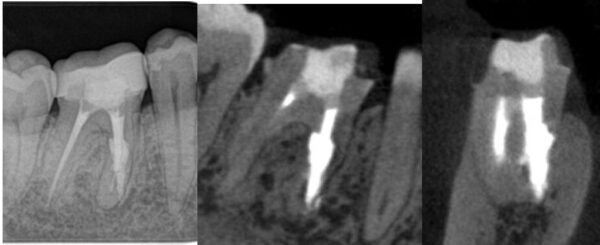

症例3: 30代女性の右下6に発症した内部吸収(黄色矢印)。大臼歯でも歯根吸収が発症する可能性がある。歯根の形が複雑な大臼歯は治療がより難しくなる。

術後2年経過時のレントゲン像とCBCT画像:吸収部位は修復され周りの骨の像は正常で経過良好です。

CBCT画像、吸収窩に充填材がしっかり充填されていることがわかる。